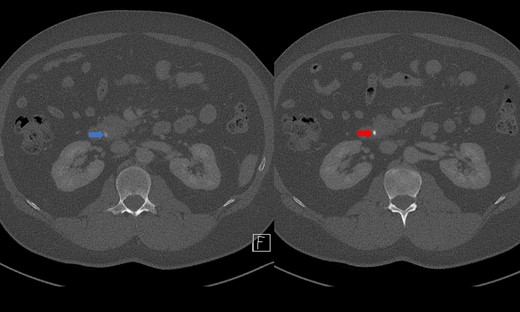

Portal venous contrast enhanced computed tomography (CT) of the abdomen revealed a layered dependent hyperattenuating material within the biliary tree (Fig. 1). The common bile duct (CBD) was dilated measuring 7.5 mm in diameter and filled along its course with radiodense material. Mild distention of the cystic duct and intrahepatic biliary tree were also noted with a 4 mm calculus in the CBD at the level of the duodenal ampulla (Fig. 2). There was no radiological evidence of cholecystitis.

CT demonstrating an obstructing calculus (right image) present within the CBD distinct from the limy bile (left image) (WW 2249, WL 450).